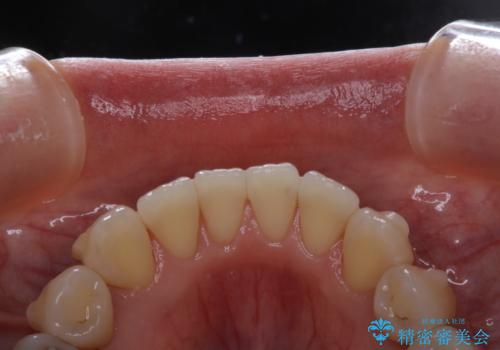

PMTCは30分コース・60分コースがあります。

30分コースでは主に前歯をメインに行います。

60分コースでは全体的に行います。

お口の状態、ご希望に合わせて当日担当の歯科衛生士とご相談してから行うことが可能です。

※着色や歯石の量、お口の状態により60分コースでも全ての汚れを除去することができない場合もあります。